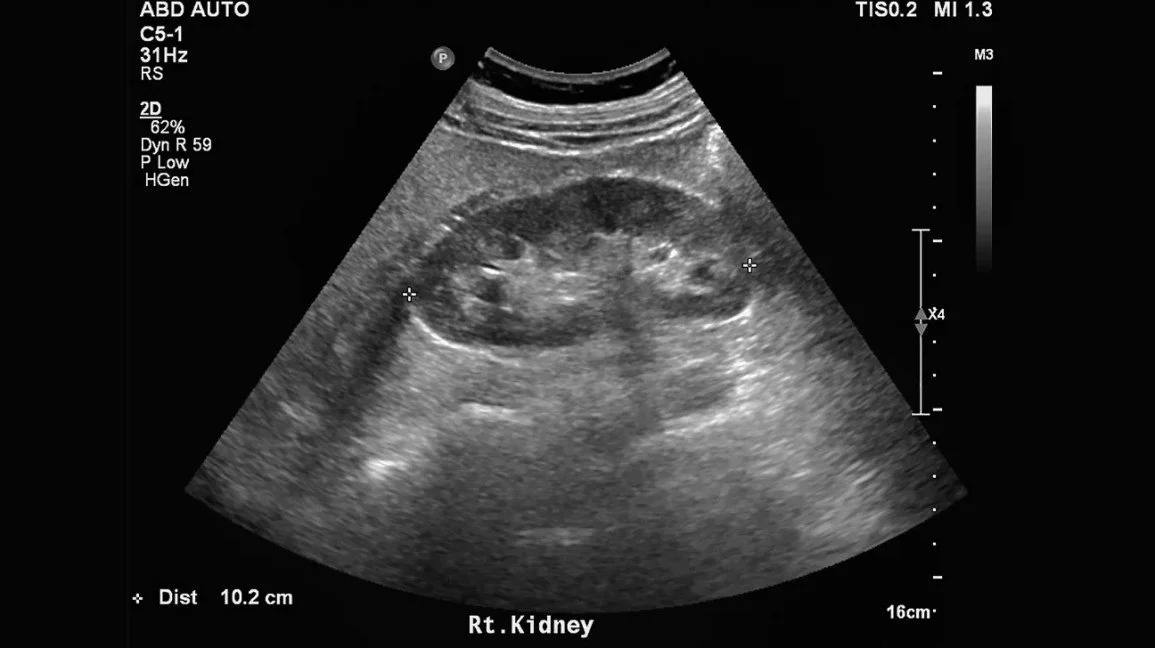

I was stunned. A few hours later, I had a (painful) kidney ultrasound. Dr. Al returned the following morning and let me know that I had no permanent kidney damage and Dr. Platinum would review everything again but I would be home soon.

Kidney on ultrasound